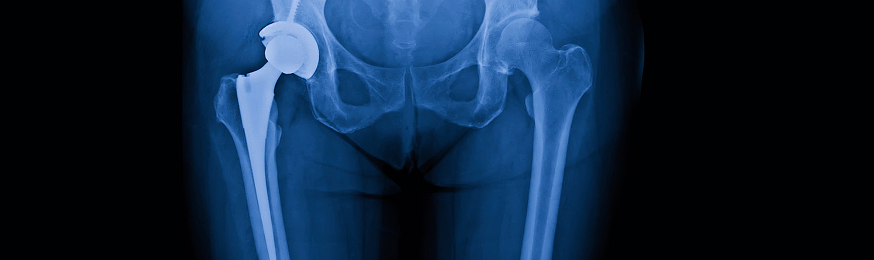

Stryker Hip

Stryker Hip Implants May Cause Metal Poisoning, Other Serious Injuries

Hip replacement surgery is usually recommended for patients suffering from (a) osteoarthritis, (b) rheumatoid arthritis, or (c) fractures. Some patients who received Stryker implants have had to undergo costly revision surgeries to correct the problems with the Trident and Rejuvenate devices. Others have simply endured the pain, discomfort, swelling and diminished quality of life.